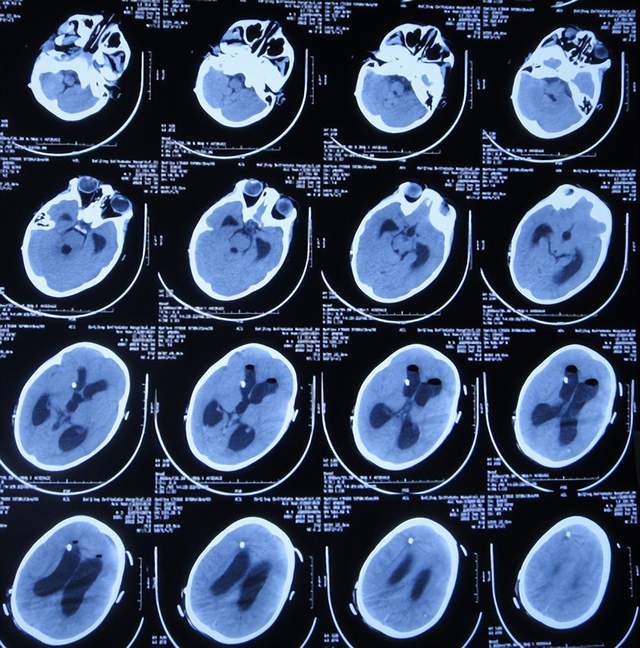

入院当天查头颅CT示脑室扩张(图-8)。

图-8:2022年7月1日入院时头颅CT

入院次日进行了脑室外引流术(图-9);引流出的脑脊液浑浊有絮状物(图-10)。

图-9:2022年7月2日头颅CT

住院治疗18天即2022年7月18日,查头颅CT示脑室有缩小(图-12)。

图-12:2022年7月18日头颅CT

2022年10月12日(住院治疗104天),已夹闭脑室引流管3天,查头颅CT示脑室未见异常(图-17)。

图-17:2022年10月12日头颅CT

2022年10月19日(住院治疗111天),拔除了脑室引流术,拔管前和拔管后头颅CT(图-18)对比。

图-18:2022年10月19日拔管前后头颅CT对比